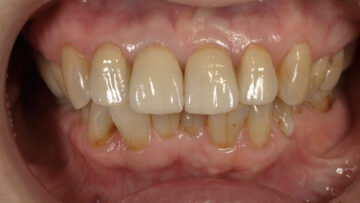

術前

術後

[治療内容] 上①1② Br:ジルコニアセラミック修復 [主訴] 他院で入れた仮歯の見た目が気になる [目的] 見た目の改善 [副作用・リスク] セラミックが破折する可能性がある [治療期間(回数)] 約4ヶ月 [費用(税抜)] ¥420,000(内訳 ジルコニアセラミック¥140,000×3本)